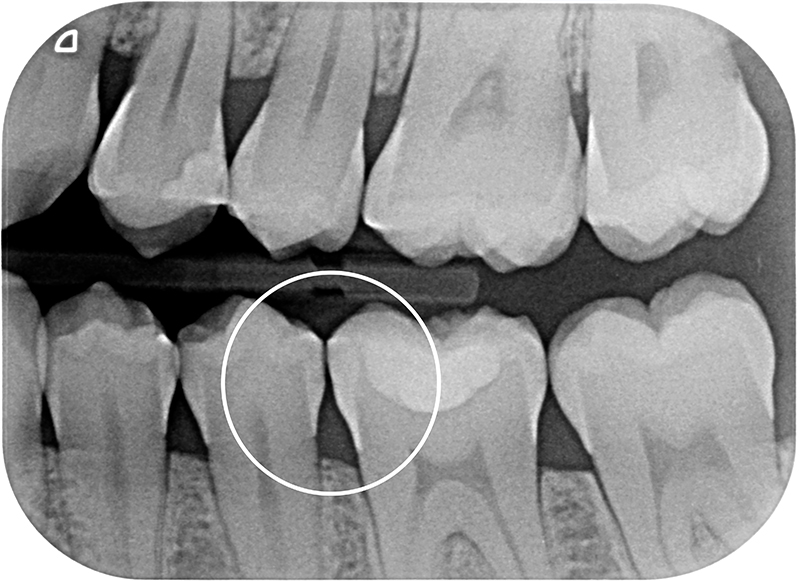

In una paziente di 30 anni, durante un esame radiografico di routine viene rilevata una lesione cariosa interprossimale cavitata sul 36 mesiale ed una lesione cariosa interprossimale non cavitata sul 35 distale coinvolgente radiologicamante la metà interna dello smalto (E2, Fig. 7 e Fig. 8).

Fig. 7 - Immagine radiografica prima dell’applicazione, lesione cariosa interprossimale cavitata

sul 36 mesiale e non cavitata sul 35 distale.